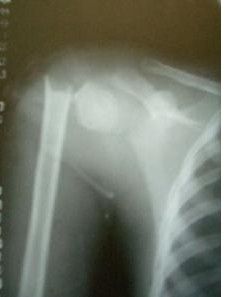

肱骨外科頸骨折 兒童的股骨幹骨折可能為不全或青枝骨折;成人股骨幹骨折後,內出血可達500-1000ml。可發生斜形、螺鏇形或青枝骨折。骨折發生的部位以股骨幹中下1/3交界處為最多,上1/3或下1/3次之。骨折端因受暴力作用的方向,肌群的收縮,下肢本身重力的牽拉和不適當的搬運與手法整復,可能發生各種不同的移位。股骨幹上1/3骨折時,骨折近段因受髂腰肌,臀中、小肌及外鏇肌的作用,而產生屈曲、外展及外鏇移位;遠骨折段則向後上、內移位。

肱骨外科頸骨折一般有受傷史,多數傷者均有較嚴重的外傷史,傷後肢體劇痛,活動障礙,局部腫脹壓痛,有異常活動,患肢短縮。合併多處傷或內臟傷及休克者較常見。肱骨外科頸骨折

骨折部疼痛比較劇烈、壓痛、脹腫、畸形和骨摩擦音和肢體短縮功能障礙非常顯著,有的局部可出現大血腫,皮膚剝脫和開放傷及出血。X線照片可顯示骨折部位、類型和移位方向。